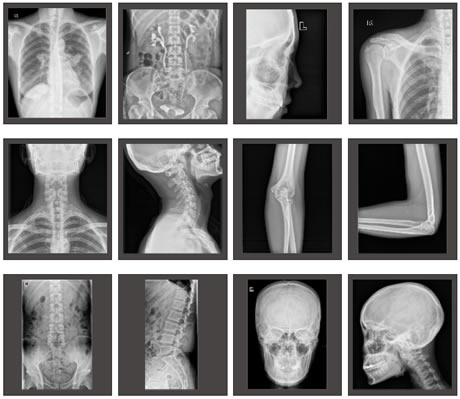

Applications

Images cliniques